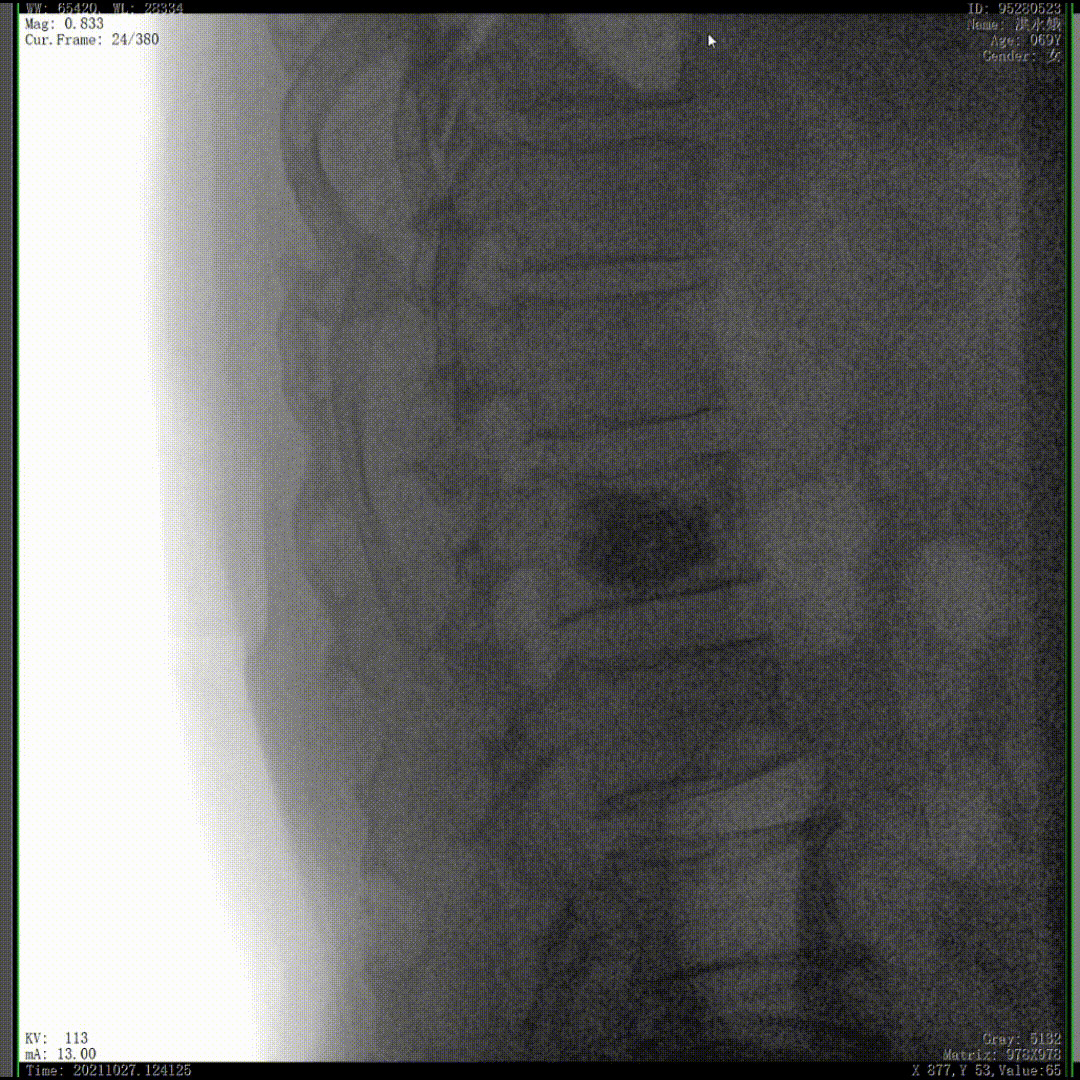

醫生通常會在“貓眼”里尋找進針點和出針點,憑醫生的經驗把釘子打在椎弓根里。手術比較依賴醫生的經驗,萬一出現偏差對病人來講就是毀滅性的打擊。如果在復雜的手術中有三維影像的支持,確保釘子精準的打在椎弓根里,可大大的提高手術操作的精度。

通常上頸椎的手術是非常復雜的,因為醫生要把釘子打在上頸椎這樣一個很狹小的通道里面,周圍都是重要的神經血管,一旦損傷到頸椎,就有可能造成病人的死亡。隨著醫學影像技術的不斷發展,在三維影像的引導下,整個打進去的通路能夠完全的展現在我們的眼睛里,讓這種復雜的手術變得簡單了,更多的醫生就可以去開展這樣的手術了,也會有越來越多的病人從中獲益。

我們完成了椎體成形術以后,在二維的正側位影像上還不能看清骨水泥的滲漏情況,通過三維影像就可以360°的觀察骨水泥在椎體里到底是怎么彌散的。如果當時我們判斷出來質量不好,可能還需要進行翻修,這是在二維影像上不能看到的。